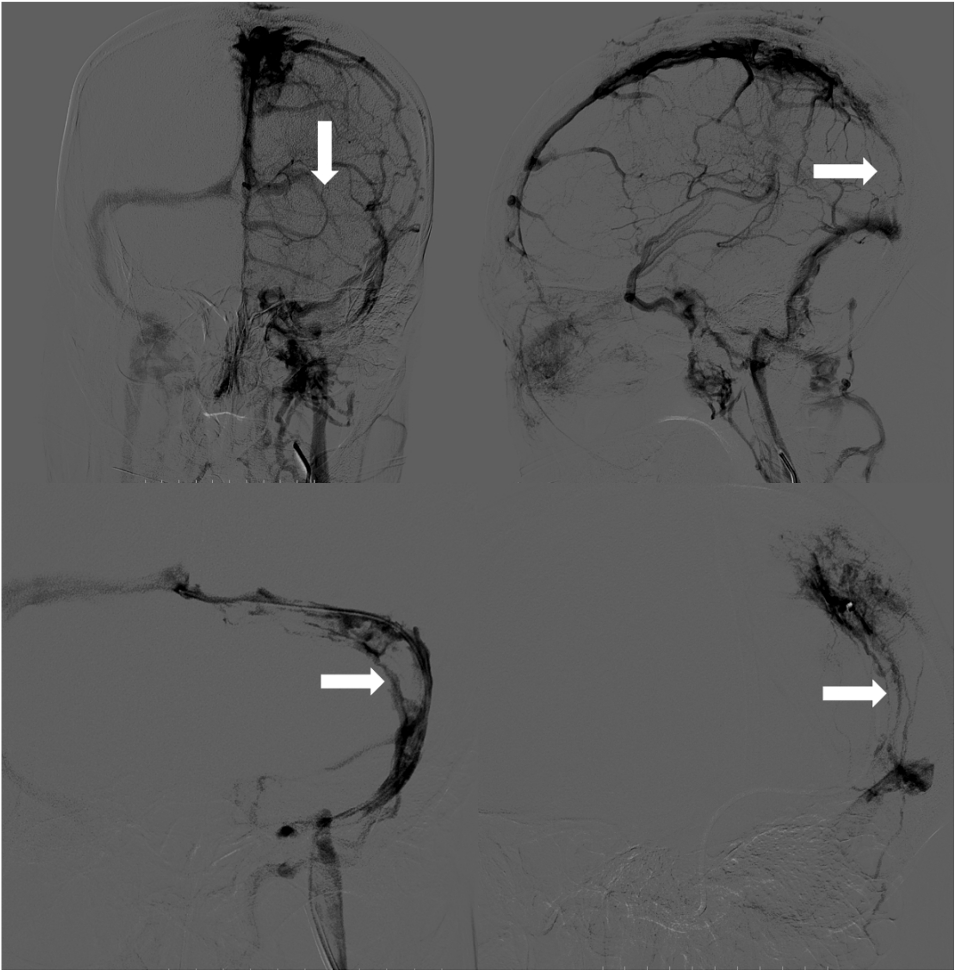

在静脉窦内造影显示血栓负荷量明显减少,静脉窦再通, 再次动脉造影显示静脉窦内血流恢复,窦内血流稍慢。

静脉窦内正向血流恢复,静脉窦内留置两根Echelon10微导管持续尿激酶溶栓,头端分别在上矢状窦和左侧横窦,造影确定位置。

术后停用口服抗凝药,经两根溶栓微导管分别给予50万单位尿激酶持续泵入,经导引导管给予5000U肝素持续泵入,持续6天。 患者术后第2天意识恢复正常,并诉头痛减轻,复查头颅CT未见出血。

术后第6天复查动脉造影,计划必要时调整溶栓导管位置,显示静脉窦内血栓完全消失,遂拔出导管和鞘管。

6月随访患者未诉不适,MRS 0分,复查MRV见静脉窦再通良好。